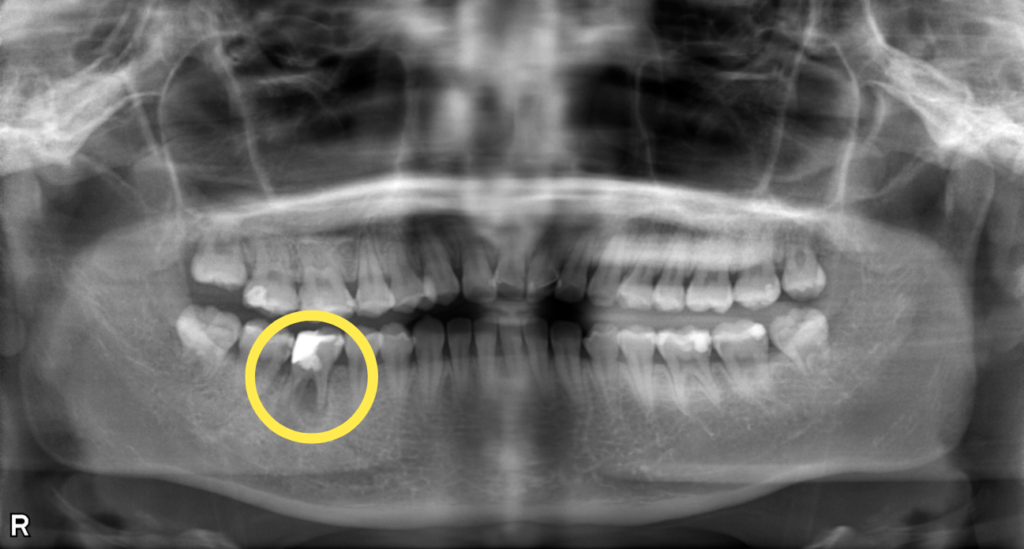

右下がかむと痛い・むし歯治療希望とのことで来院されました。 右下6番は根管内に感染を起こして根尖部に透過像を認めました。 根尖病変が非常に大きく、根管も複雑な形態をしていたため、まず歯科用CTを用いて3次元的な診断をしたのち、ルーペを使用して感染源の徹底的な除去および精密な根管治療を実施しました。 術後の経過は良好で、透過像も消失しています。根管治療後は、強度と審美性を兼ね備えたジルコニアクラウンで最終補綴を行いました。

| 概要 | 前歯に穴が開いているので治療して欲しい・右下がかむと痛いとのことで来院されました。 右下6番は根管内に感染を起こして根尖部に透過像を認めました。 根尖病変が非常に大きく、根管も複雑な形態をしていたため、まず歯科用CTを用いて3次元的な診断をしたのち、拡大ルーペを使用して感染源の徹底的な除去および精密な根管治療を実施しました。 術後の経過は良好で、透過像も消失しています。根管治療後は、強度と審美性を兼ね備えたジルコニアクラウンで最終補綴を行いました。 |